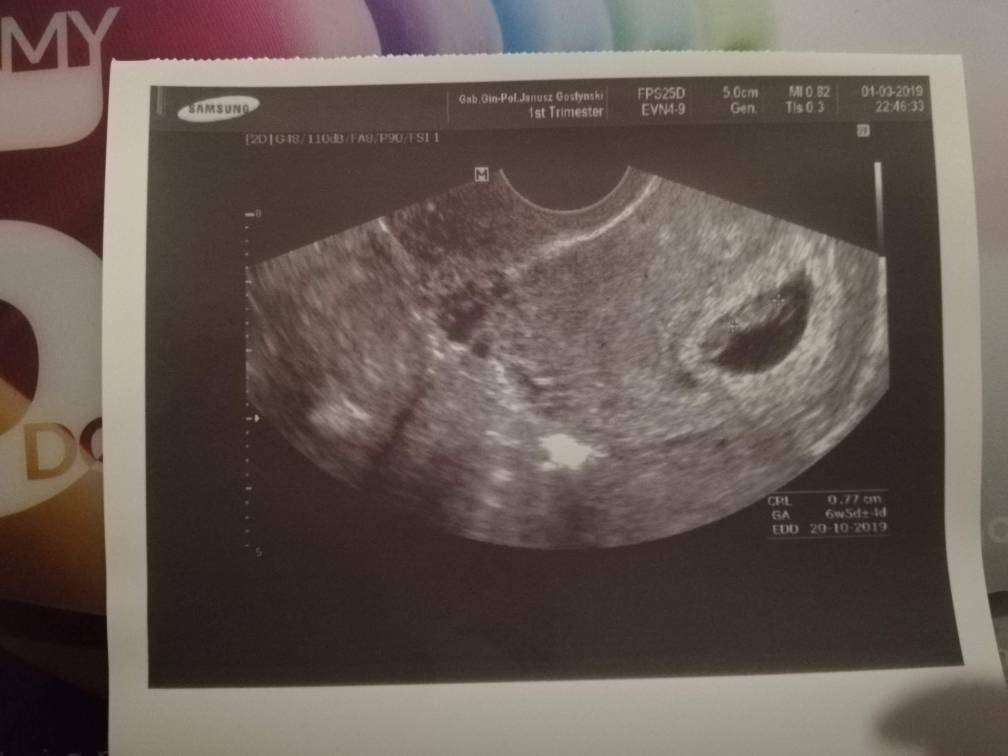

mój był dziś podobny